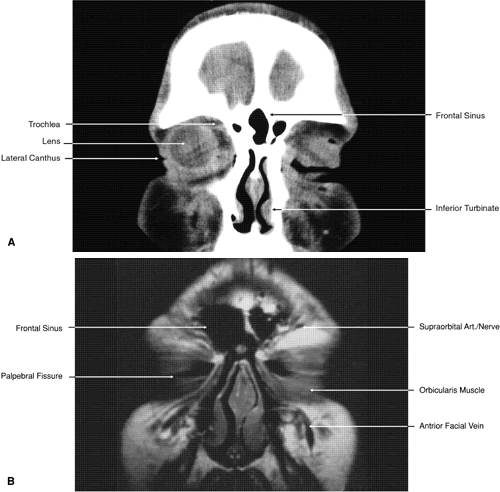

Fig. 17. Coronal images through anterior orbit. A. Computed tomography scan. B. T1-weighted magnetic resonance imaging.

Fig. 18. Coronal images through midglobe. A. Computed tomography scan. B. T1-weighted magnetic resonance imaging.